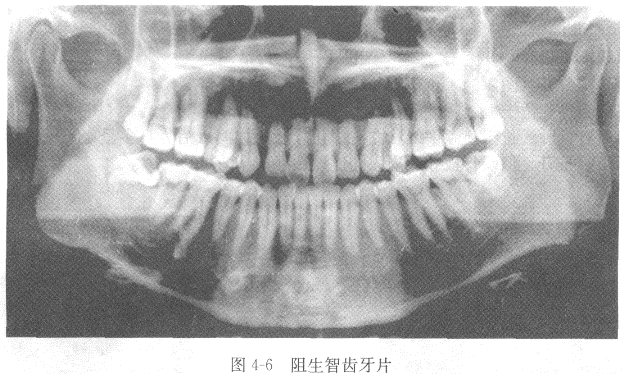

28、阻生智齿牙片(图4-6)

【答案】(1)确定阻生智齿的位置低位或高位阻生;部分或全部阻生;软组织内阻生或骨内阻生。

(2)确定阻生智齿的方向前倾位、后倾位、水平位、垂直位、倒向位。

(3)阻生智齿牙体情况及根尖有无炎症。

(4)牙根数目、长短粗细及牙根有无弯曲,牙根有无粘连,根分叉大小。

(5)阻生牙与邻牙的关系及牙根与下牙槽神经管的关系。

【解析】(1)确定阻生智齿的位置低位或高位阻生;部分或全部阻生;软组织内阻生或骨内阻生。